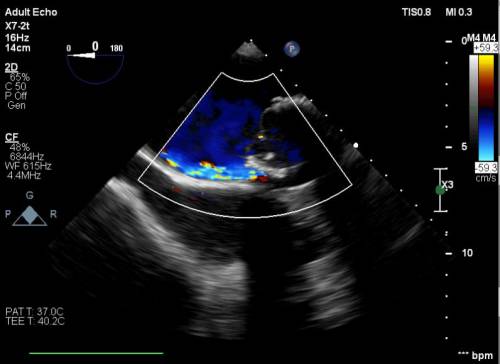

Yapılan işlemi gerçekleştiren ekipte yer alan Prof. Dr. Halil Kısacık, Doç. Dr. Eyüp Avcı, Doç. Dr. Tarık Yıldırım ve Doç. Dr. Özgen Şafak konu hakkında açıklamalarda bulundu. Daha önce kalp kapakçığı değişim ameliyatı olan hastada takılan kapağın kenarından ayrılmasıyla kan kaçağı (paravalvuler leak) meydana geldiğini belirten öğretim üyeleri, Kardiyoloji Anabilim Dalına başvuran hastaya, Türkiye’de sayılı kalp merkezinde yapılan ve önemli düzeyde cerrahi deneyim gerektiren paravalvüler kaçak kapatılması işlemi uygulandığını dile getirdi. İşlemin sadece girişimsel kardiyologlar tarafından yapıldığının altını çizen öğretim üyeleri, işlem sırasında hastanın kalbi durdurulmadan ve göğüs kafesi kesilmeden, kasığından girilerek yapay kalp kapağındaki kaçağın ameliyatsız kapatıldığını söyledi.